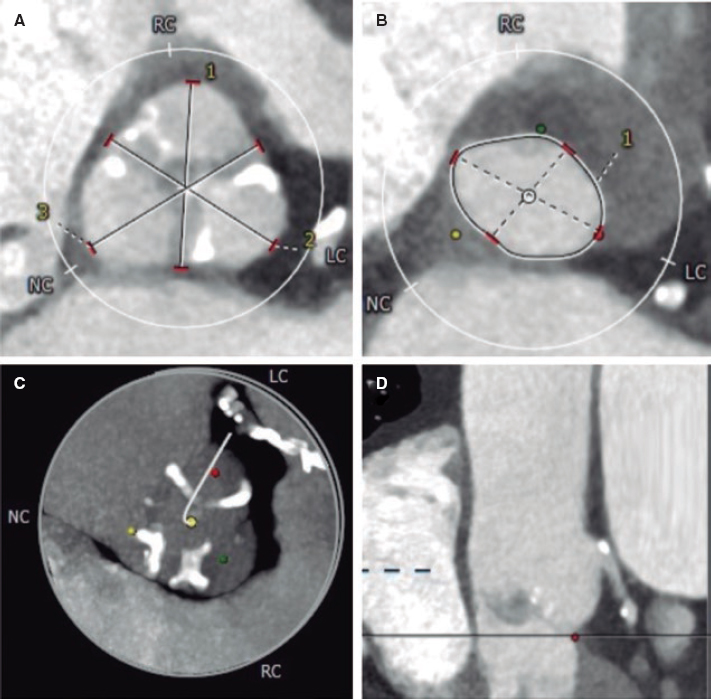

The evolution of the patient was not favorable, brain death was declared 24 h after admission, and the patient was eventually declared dead. The microscopic analysis of the coronary aspirate revealed the presence of mesenchymal tissue with myxoid changes consistent with tumor embolism (figure 1) whereas the macroscopic piece confirmed the diagnosis of atrial myxoma (figure 2, arrow).

Figure 1. The red arrows point at the fibrinoid tissue. The blue arrows point at the mesenchymal tissue with myxoid changes.